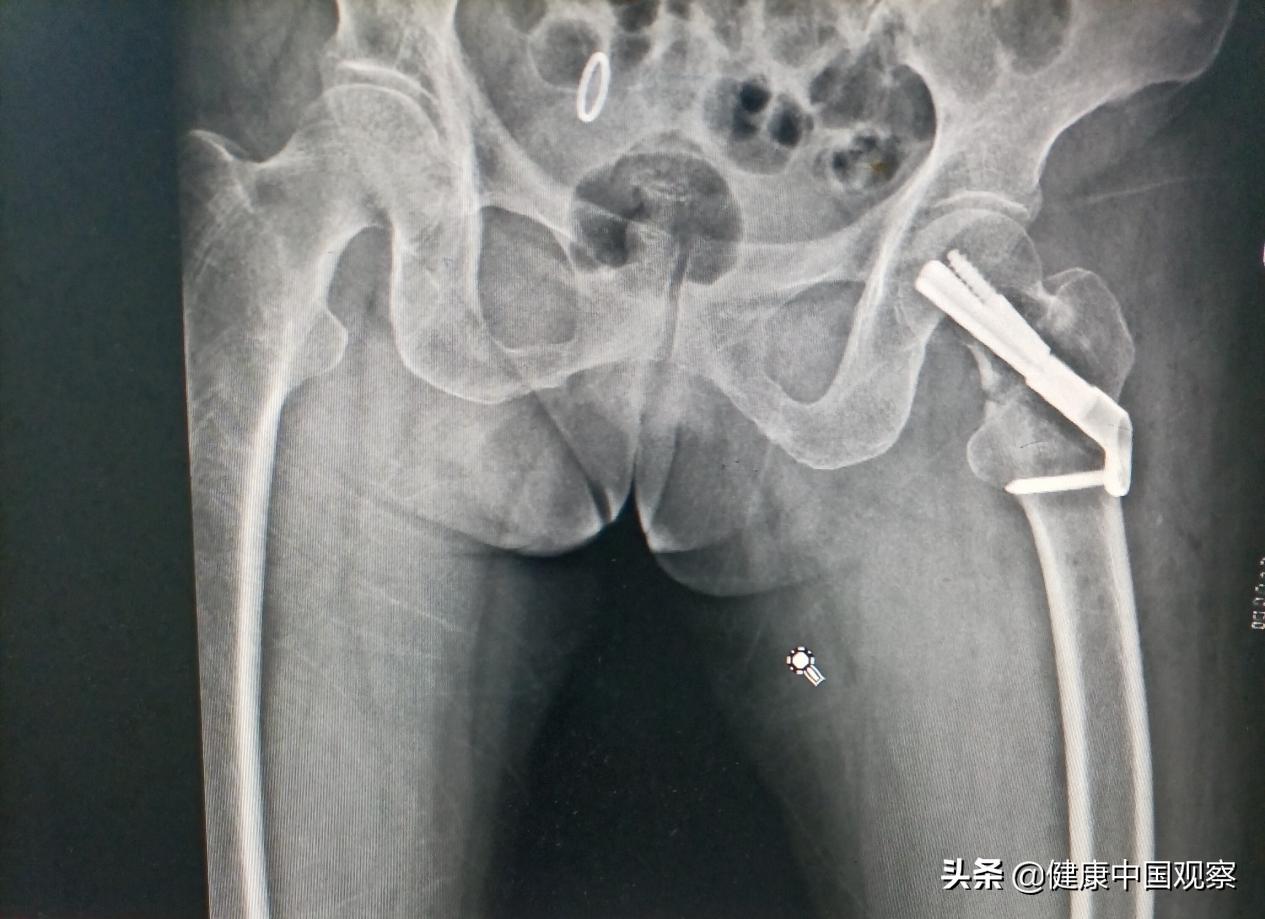

患者郁女士今年已70岁。7月27日,患者因不慎摔倒导致左髋部疼痛并且左下肢活动受限。在家人陪伴下,患者来到医院就诊,经检查后被诊断为左侧股骨颈骨折,随后住院治疗。

医院骨科团队杨永辉主任医师、王剑玮副主任医师和邱卫华副主任医师在详细检查病人和阅片后,一致认为患者虽然为老年人,但是股骨颈骨折类型为股骨颈基底部骨折,考虑做股骨颈骨折闭合复位FNS内固定术,可以保留患者自己的髋关节,避免人工全髋关节置换或人工股骨头置换的一些并发症。

结合综合评估,并与患者和家属详细沟通之后,骨科团队做好了充分的术前准备。骨科团队于7月30日上午为患者做了左股骨颈骨折闭合复位FNS内固定术,整个手术过程顺利,骨折闭合复位和置钉位置均成功,手术时间仅用了不到1个小时,切口也仅仅只有5厘米左右。目前患者恢复良好,近日可以出院。

此次手术所采用的FNS内固定系统为一种新型股骨颈内固定系统,股骨颈动力交叉钉系统(FNS)结合了滑动式髋螺钉和多枚空心钉内固定的优点,将动力棒和抗旋螺钉整合在同一个钉空中,同时具备角稳定和抗旋稳定。此外,动力棒和抗旋螺钉相互锁定,具备动力加压的作用可有效降低内固定切出或者穿出股骨头。该技术通过微创手术技术,实现了骨折复位后固定的稳定性,手术创伤小、稳定性好,有利于早期康复、早期负重、早期功能锻炼,降低股骨颈骨折不愈合发生率,是目前国内国外股骨颈骨折最新的一种治疗方法。